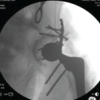

The operative procedure was considered for radial head displaced fractures with more than one fragment, limited supination or pronation, impaired forearm motion, fracture displacement more significant than 2 mm, or when more than one-third of the radial head diameter was fractured [10-14]. All patients underwent surgery using a lateral approach, modified based on Kaplan’s method, which involves operating between the extensor digitorum communis and extensor carpi radialis brevis muscles [15]. The treatment method was selected according to the fractures’ instability and complexity, which were determined using the Hotchkiss modification of the Mason classification. Simple two-part fractures were stabilized with 2 mm headless screws, while more complex, multi-fragmentary fractures were managed with 2.4 mm locking compression radial head plates and 2.0 mm radial head plates. For example, typical cases, including pre-and post-operative X-rays showing screw osteosynthesis for Mason type II fractures, are shown in Figs. 1 and 2, respectively.

The pre- and post-operative X-rays showing plate osteosynthesis for Mason type III fractures are shown in Figs. 3 and 4, respectively.

The muscles attached to the posterior supracondyles were released to obtain a complete view of the radial head. In lateral collateral ligament injury cases, suture anchors are used to reattach the ligament to the lateral epicondyle of the humerus. Cortical positioning screws, sized 1.5 mm to 2.0 mm and starting from 18 mm to 34 mm in length, have been used. The wide variety of screws is determined intraoperatively and placed transversely or obliquely as bicortical positioning screws without compression [16]. 10 out of 12 patients have been treated with ≥2 screws, treated with 4 screws (3 out of 30), and two affected person changed into dealt with a single screw (Figs. 1 and 2). There was no need for bone grafting in any individuals.